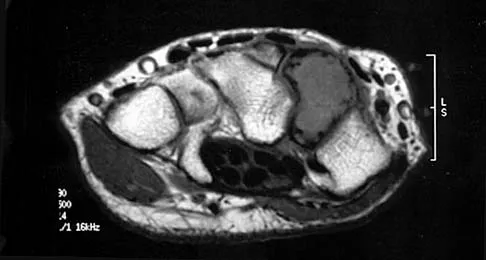

A patient has right shoulder pain. Figure 1a shows a gadolinium-enhanced transverse MRI scan at the level of the coracoid. Figure 1b shows an arthroscopic view of the anterior structures from a posterior portal. These images reveal which of the following findings?